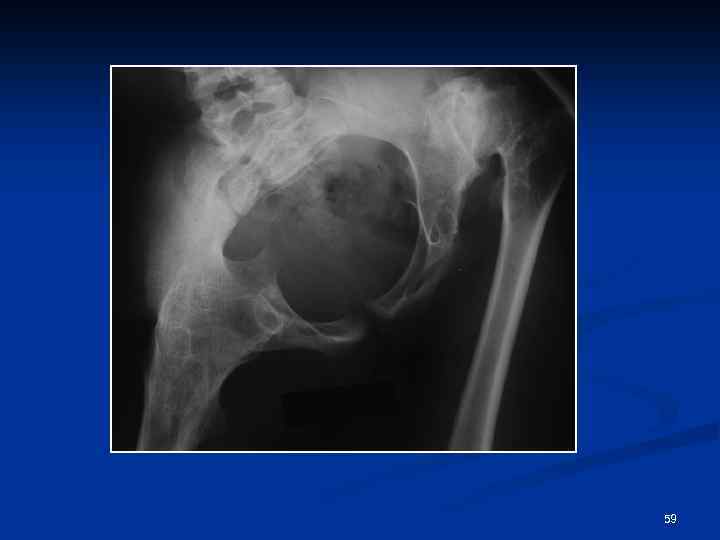

Костный анкилоз Отсутствие рентгеновской суставной щели n Переход костных балок с одной кости на другую n Отсутствие компактных замыкательных пластин n 58

59

Нарушение нормальных соотношений в суставе, изменение высоты рентгеновской суставной щели подвывих 60